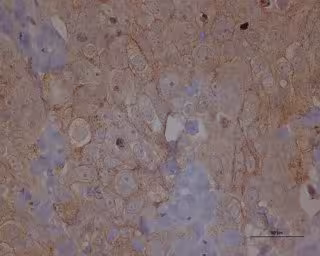

IDIBELL-ICO - Archivo